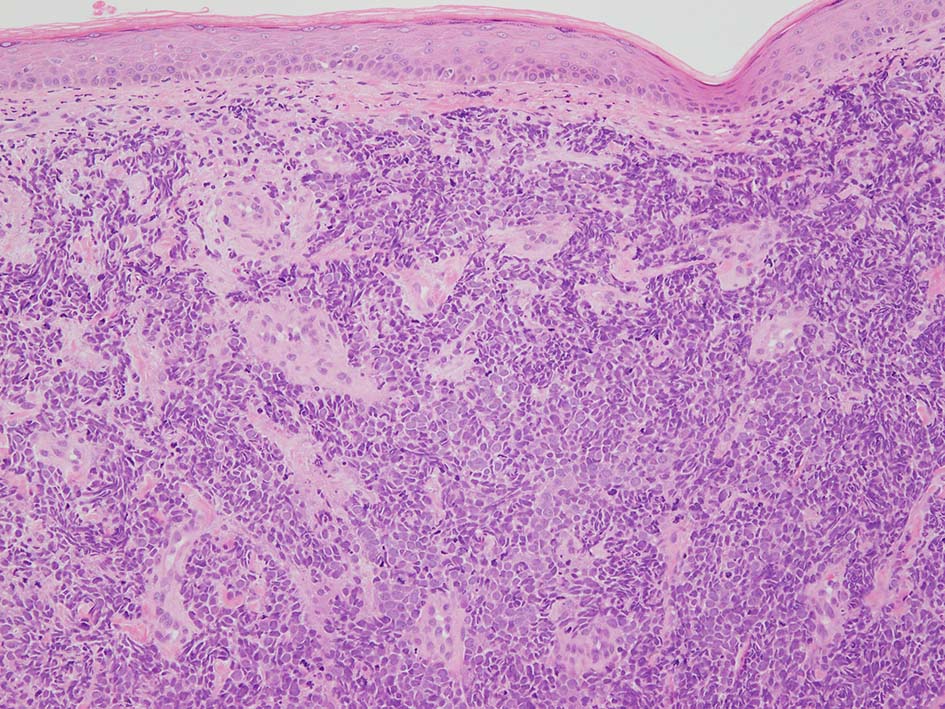

皮膚原発性Merkel細胞癌は 通常真皮を病変首座に増殖し, しばしば脂肪織まで浸潤する.

表皮とは連続性がなくGrenz zoneがみられるのが特徴であるが, 病理所見は多様であり, ときに表皮向性を示す症例やpagetoid patternを呈する症例もある.

典型的な腫瘍細胞は円形, 卵円形の比較的均一な形態で「salt-and-pepper」と称される微細顆粒状クロマチンを有する小型円形核をもつ. MCPyV陽性例が均一な小型円形核を呈する傾向があり, 陰性例では, 核多形性が目立つととする報告がある.

loupe像 HE

HE